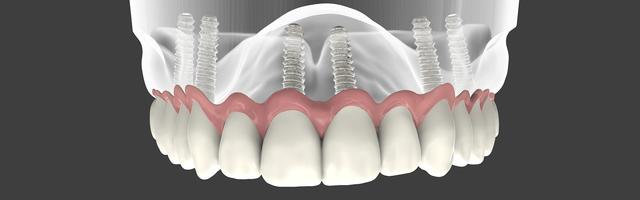

“ I have been aware of having gum recession for quite a few years now, but my dentist said that currently there is no cure for this condition. He said you can prolong the problem, but you cannot really cure it. All of my upper and lower teeth are moving as a result, and one of them has become so loose as a result of biting that it is ready to fall out at any second. I simply must remedy this situation, for aesthetic reasons as well as medical ones. Because all of my teeth are loose, a partial bridge is out of the question, but I do not want a denture. Your website mentions the Imtec-MDI row of teeth with 4 miniature dental implants. This solution looks feasible. What is the difference between mini and normal dental implants?”